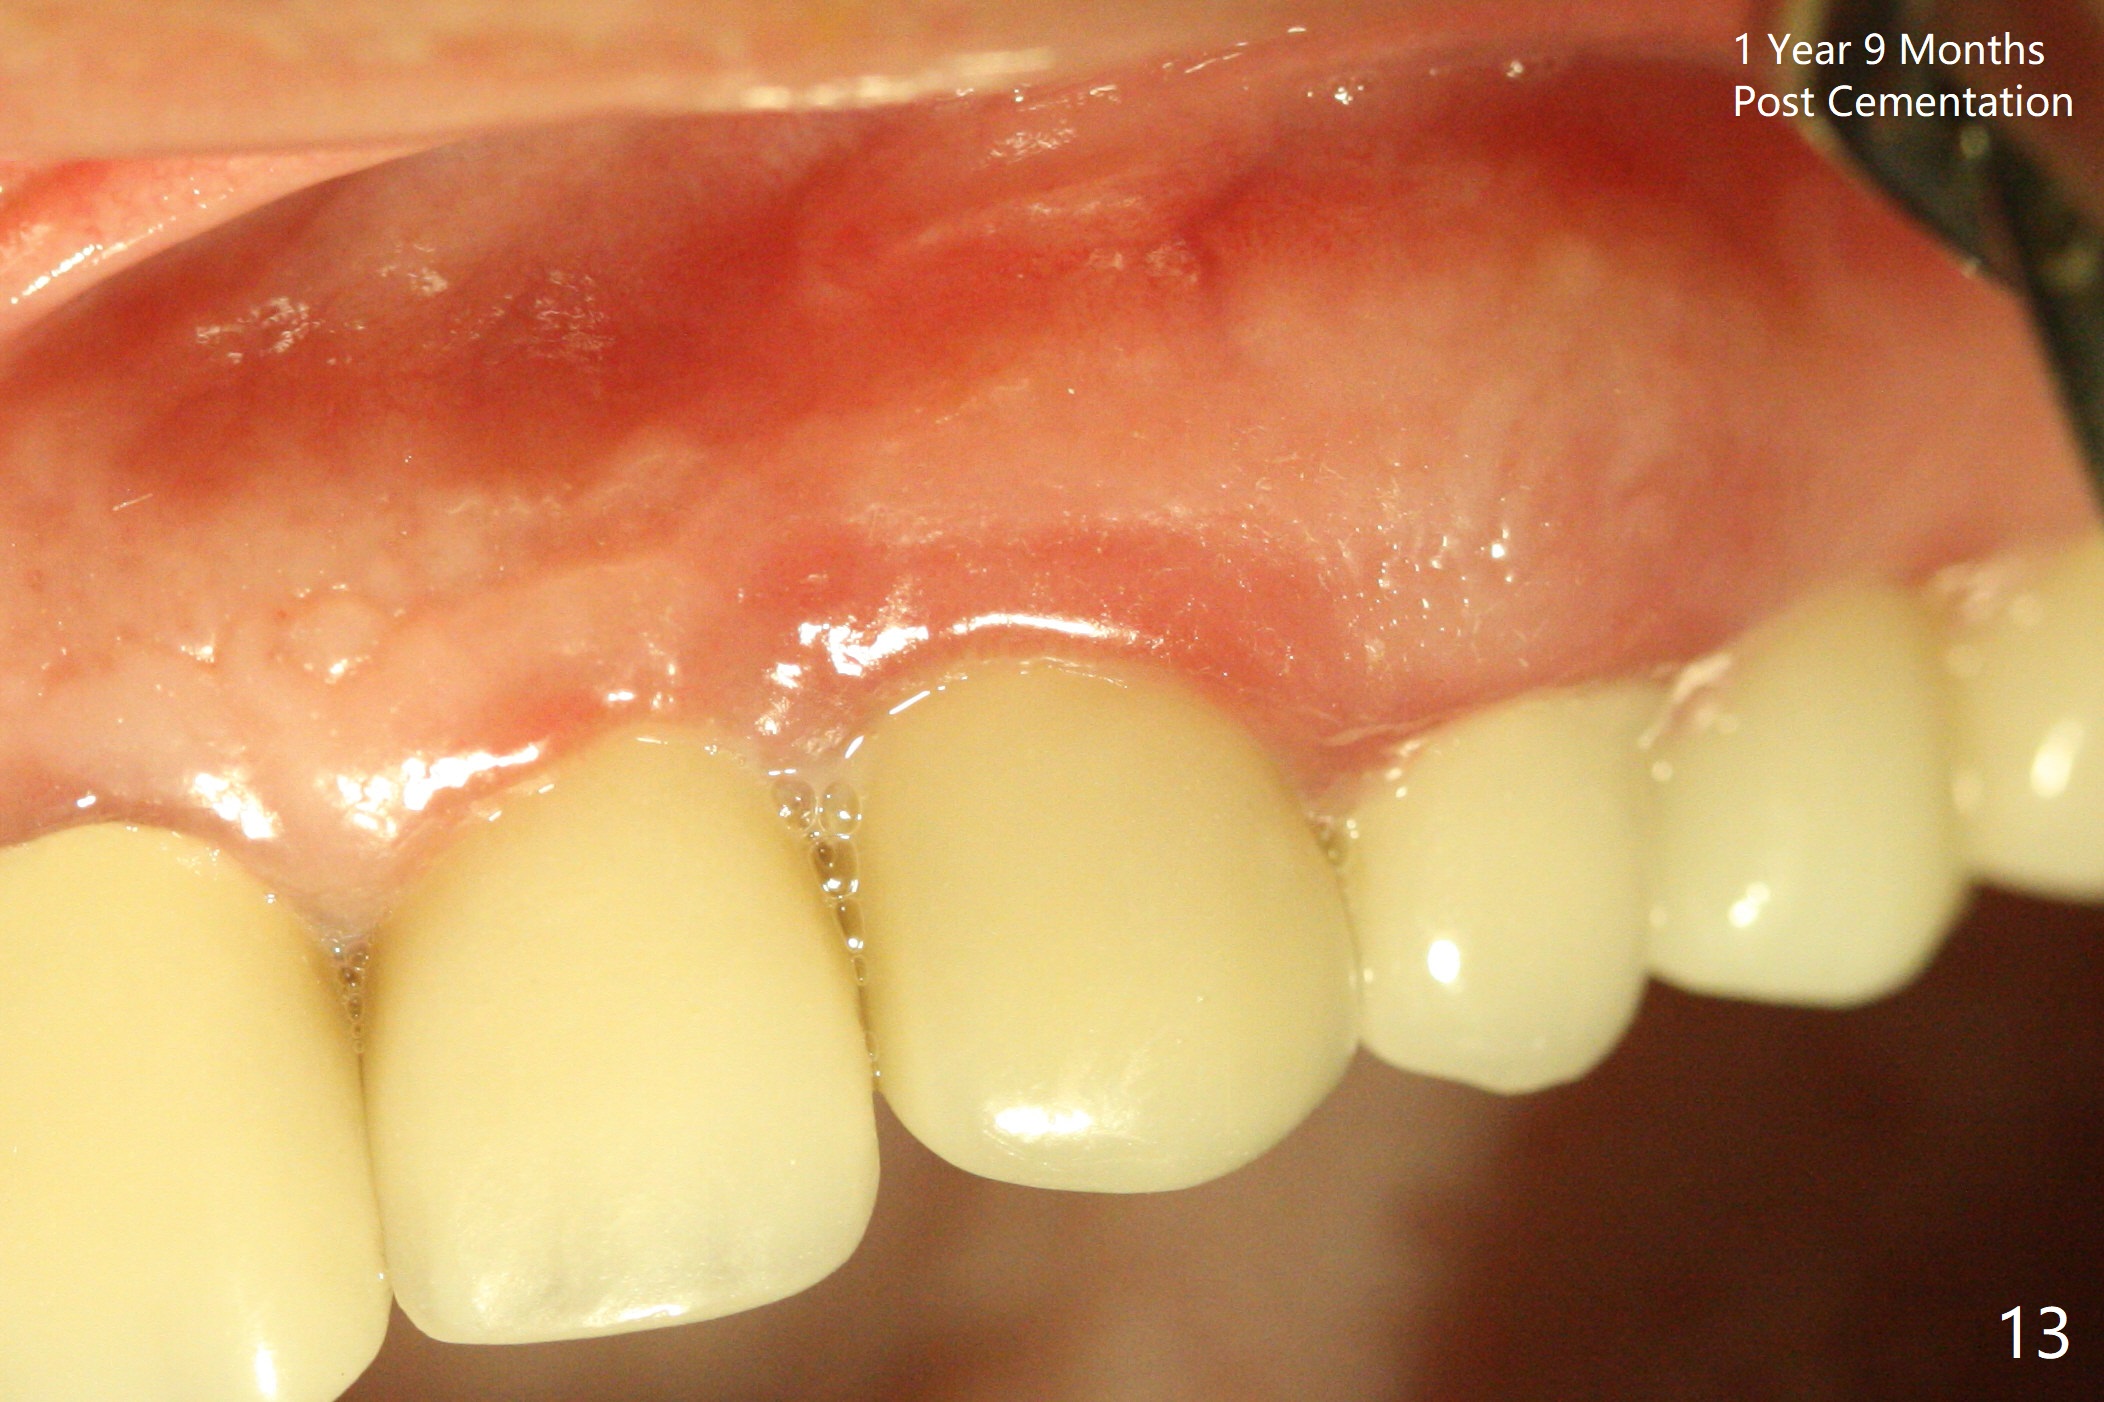

In spite of severe apical infection (Fig1,2 *), a thin narrow strip of the buccal plate (arrowheads, corresponding to the keratinized gingiva) is present when the tooth #11 is extracted. The thin bone keeps the bulging alveolus, i.e., reservoir for bone graft (Vanilla/Osteogen Fig.4 *) after placement of a 3.8x16 mm implant (Fig.3,4). A 4.5x1 mm temporary abutment, placed and trimmed for an immediate provisional, seems to be short in cuff. When an implant is placed deep to prevent periimplantitis, the cuff should be longer, i.e., 3 mm. X-ray should be taken for the depth confirmation after temporary abutment placement. Eight days postop, the mesial gingiva erythema has subsided (Fig.5 < (P: provisional)), while the apical swelling is no longer tender and most likely due to packed bone graft (*). Panoramic X-ray taken 2 weeks postop shows the clearance from the nasal cavity or the maxillary sinus (Fig.6). While the hard tissue around the implant seems to be healthy 5 months postop (Fig.7), the soft tissue is not (Fig.8). The temporary abutment is changed to a cemented one (4.5x5(2) mm) for impression (Fig.8). Since the neighboring crowns are PFM (Fig.6), the new crown will be made of the same material for shade match. Indeed PFM helps shade match in this case as well (Fig.9,10). Switching abutments (from temporary to cemented) makes it difficult to seat the crown. Post cementation X-ray leaves record for future contact loosening. The buccal gingiva remains erythematous associated with open margin (Fig.11 >) 1 year 4 months post cementation. There is no obvious bone loss 1 year 4 months post cementation (Fig.12). It appears that the crown and abutment need to be changed. Although the gingival margin remains erythematous, the gingival hemorrhage is basically lacking due to better oral hygiene during Shelter at Home (1 year 9 months post cementation, Fig.13). Change in abutment and crown will be conducted post coronavirus pandemic. In fact the abutment is incompletely seated (Fig.14 <). In addition, the tooth #12 is symptomatic with PARL associated with the buccal root (*). CBCT indicates possible buccal root fracture (Fig.15,16 ^) and loss of the buccal plate (Fig.16 <).